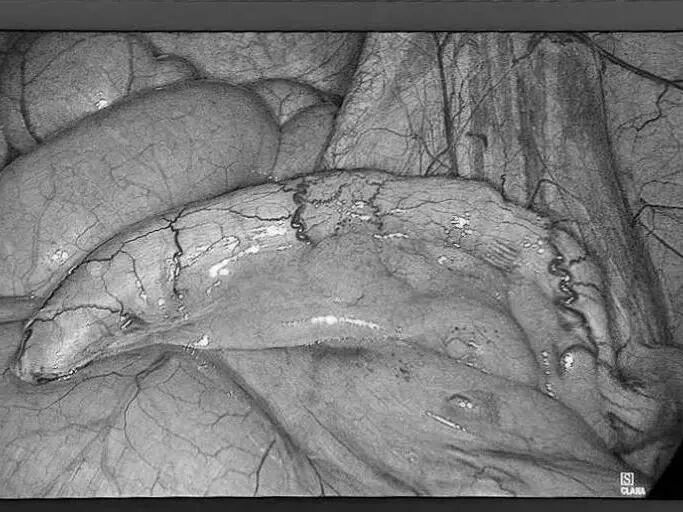

多年来,贵州航天医院各科室紧跟医学前沿,不断强技术、补短板,大力开展新技术、新项目,完成了许多高精尖、高难度、本地区“首例”的技术,填补了医院医疗技术空白,满足了群众日益增长的医疗需求。 本期,我们将为大家带来普外科特色技术——腹腔镜下腹股沟疝无张力修补术(TAPP)。 案例分享 患者在两年前检查发现双侧腹股沟区可复性包块,因当时症状较轻,偶有疼痛,患者未予重视,最近几个月,疼痛愈发频繁,严重影响了工作和生活,故前来我院普外科就诊。科室为患者完善了超声等相关检查后,明确诊断为:双侧腹股沟疝。 在充分与患者进行沟通同意后,制定并成功实施了腹腔镜下腹股沟疝无张力修补术治疗的方案,术中出血量少,术后第三天顺利出院。 腹腔镜下腹股沟疝无张力修补术(TAPP)能在无张力的情况下,利用人工高分子材料网片进行修补,具有术后疼痛轻、恢复快、复发率低等优点,已成为目前患者选择最多的疝修补术。 什么是腹腔镜下腹股沟疝无张力修补术 像用“补丁”补衣服一般,用人体组织兼容的高分子材料进行“补片”,由于不是强行拉合疝洞两边的组织,而是将补片覆盖腹股沟疝的缺损,所以组织间不产生张力,最大限度地保留了人体原有的生理结构和组织层次。同时,补片多呈网状结构,能起到支架作用,使人体自身的组织沿着补片支架生长。 腹腔镜下腹股沟疝无张力修补术原理 通过三个仅0.5 -1cm 的小切口进入腹腔,打开腹膜后将疝囊回纳,利用腹腔镜和专用器械在腹膜前间隙植入补片,覆盖肌耻骨孔,关闭腹膜后完成疝修补操作,有效减小了患者手术创伤。 腹腔镜下腹股沟疝无张力修补术优势 (一)修补结实,损伤更小。 (二)具有符合生理学的优势,术后不适感减少。 (三)保持局部组织结构层次,为再发疝或其他疾病留下治疗余地。 (四)能全面观察病情,发现无明显症状的隐匿疝,避免遗漏。 贵州航天医院普外科专家团队 梁 跃 中共党员,普外科党支部书记、主任,主任医师 临床擅长:对普外科各类肿瘤手术具有丰富的临床经验。 毕业于遵义医学院,遵义市医学会小儿外科学分会常务委员,遵义市肛肠协会理事,遵义市医学会核医学分会(第二届)委员会委员;荣获第三期“黔医人才计划”优秀学员称号;主持市级课题1项,完成省级课题1项,在国内各类刊物上发表论文10余篇。 钱科洪 民盟盟员,普外科副主任医师 临床擅长:从事普外科临床工作30余年,对各类普外科疾病的诊治、乳腺、甲状腺、胃十二指肠、结直肠等疾病及疑难杂症具有丰富的临床经验。 毕业于遵义医学院临床医疗系,2009年前往中山大学附属第一医院微创外科进修学习,在国内各专业期刊发表论文数篇。 贵州航天医院普外科简介 基本情况 贵州航天医院普外科成立于1968年,前身属于航天部O61基地3417医院外一科,1998年3417医院、3427医院合并后更名为普外科,下设胃肠外科、肛肠外科2个亚专业科室,拥有在全市较为先进的专科设备和技术,是中国疝病专科联盟单位,贵州医科大学附属医院胃肠外科专科联盟单位。开放床位40张,配备医护人员21人。 专科特色 普外科致力于胃肠及肛肠疾病的外科临床诊治及科研,以腹腔镜微创外科技术为本,形成以快速康复治疗胃肿瘤、结直肠肿瘤、小肠肿瘤、直肠脱垂、肥胖病、急腹症、各类疝、痔、瘘等专科特色,同时注重胃肠疾病尤其是结直肠恶性肿瘤的基础研究和临床转化研究,总体诊断和治疗水平在区域同级医院居于领先水平。 开展手术:腹腔镜下胃癌根治术,腹腔镜下袖状胃切除术,腹腔镜下胃肠道间质瘤切除术,腹腔镜下结、直肠癌根治术,胃癌、结直肠癌的精准治疗,腹腔镜下小儿疝气、成人疝修补术,腹腔镜下阑尾手术,内痔的硬化注射治疗及痔疮的微创治疗:ATH、PPH、TST,直肠脱垂的各种手术治疗,难治性伤口VSD技术,鼻胃肠管、肠梗阻导管置入术,肛肠术后间歇性导尿技术,并引进了中医适宜技术,也为各种化疗患者提供输液港安装,提高患者就医体验。 腹腔镜下腹股沟疝 无张力修补术 腹股沟疝里金斯坦(Lichtenstein)手术 PPH微创术治疗环状混合痔 黏连性或炎性肠梗阻-肠梗阻导管 腹腔镜袖状胃切除 腹腔镜阑尾切除术 腹腔镜阑尾肿瘤切除术 腹腔镜下结肠癌根治术 诊疗范围 胃肿瘤、结直肠肿瘤、小肠肿瘤、肥胖症、各类急腹症、腹部外伤、腹壁疝、便秘、直肠脱垂、痔疮、肛瘘、肛裂等胃肠、肛肠外科疾病。 一审一校:梁 跃、黄成成